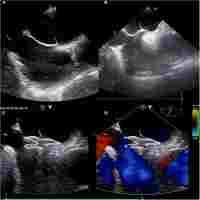

| Abstract | Background Percutaneous closure of patent foramen ovale (PFO) is routinely performed using plain fluoroscopy in the catheter room. This method results in inevitable radiation damage, adverse effects of contrast agents on kidneys, and high cost. We performed PFO closure with a simplified and economical transesophageal echocardiography (TEE)-only guided approach in the operating room. This study aimed to investigate the feasibility, safety, and effectiveness of the percutaneous closure of PFO by only using TEE. Methods We reviewed the medical records of patients who underwent percutaneous PFO closure at our center from December 2013 to December 2017. A total of 132 patients with PFO and cryptogenic strokes underwent PFO closure by using cardi-O-fix PFO device under TEE guidance. The participants comprised 64 and 68 male and female patients, respectively. The mean age and body weight of the patients were 39.40 ± 13.22 years old (12–68 years old) and 65.42 ± 9.70 kg (40–95 kg), respectively. All patients only received aspirin (3–5 mg/kg body weight, oral administration) for 6 months. Contrast-enhanced transthoracic echocardiography (c-TTE) with Valsalva maneuver was performed during follow-up, and questionnaire surveys were obtained at 3, 6, and 12 months after the procedure. Results All (100%) patients were successfully closed. Follow-ups were conducted for 13 months to 48 months, with an average of 27 months. No severe complications were found during the follow-up period. Paroxysmal atrial fibrillation occurred in 4 patients within 3 months after the procedure. No recurrent stroke or death occurred in all patients during the follow-up period. Transient ischemic attack occurred in one patient 6 months after the procedure. Ten (7.6%) patients had a right-to-left shunt, as demonstrated by c-TTE at 12 months of follow-up. Among the 57 patients suffering from migraine, significant relief or resolution was reported by 42 (73.7%) patients. Conclusion TEE-only guided PFO closure was a safe, feasible, and effective method that did not require the use of X-rays and contrast agents. |